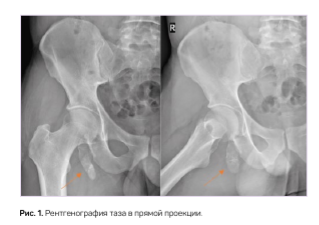

Нами было выявлено 2 случая врожденной аномалии. У пациента С. при полипозиционном рентгеновском исследовании обнаружен отдельно лежащий костный фрагмент в мягких тканях параартикулярно, имеющий фрагментарное строение. На рентгенограммах правого тазобедренного сустава при полипозиционном исследовании в области седалищного бугра определяется свободнолежащий фрагмент костной плотности, с трабекулярной структурой, с четкой замыкательной пластинкой, полигональной формы, размером 75,0 х 23,0 мм (рис. 1).